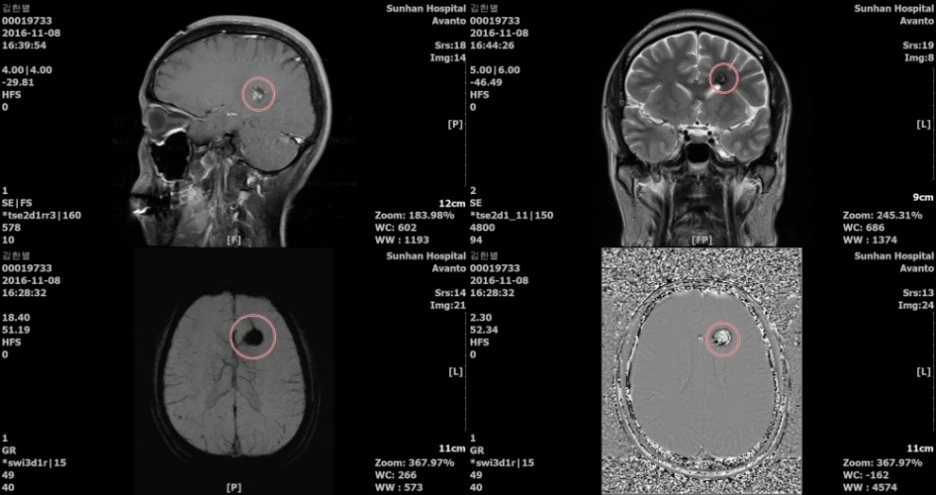

가벼운 사고였지만 교통사고 확인차 '엑스레이'와 '뇌 CT' 등을 찍었다.

의사 선생님은 조심스럽게 '뇌 MRI'를 한번 찍어보자고 하셨다.

종양으로 '의심'되는 뇌 속의 무언가가 발견되었다는 소견과 함께.

일단 혼자 입원해서 '뇌 MRI'를 찍고 정밀 검사를 했다.

결론적으로는, 정말 다행스럽게도 '혈관이 뭉쳐있는' 정도의 해프닝이었다.

(CT 상으로는 종양처럼 보이기도 한다고 한다.)